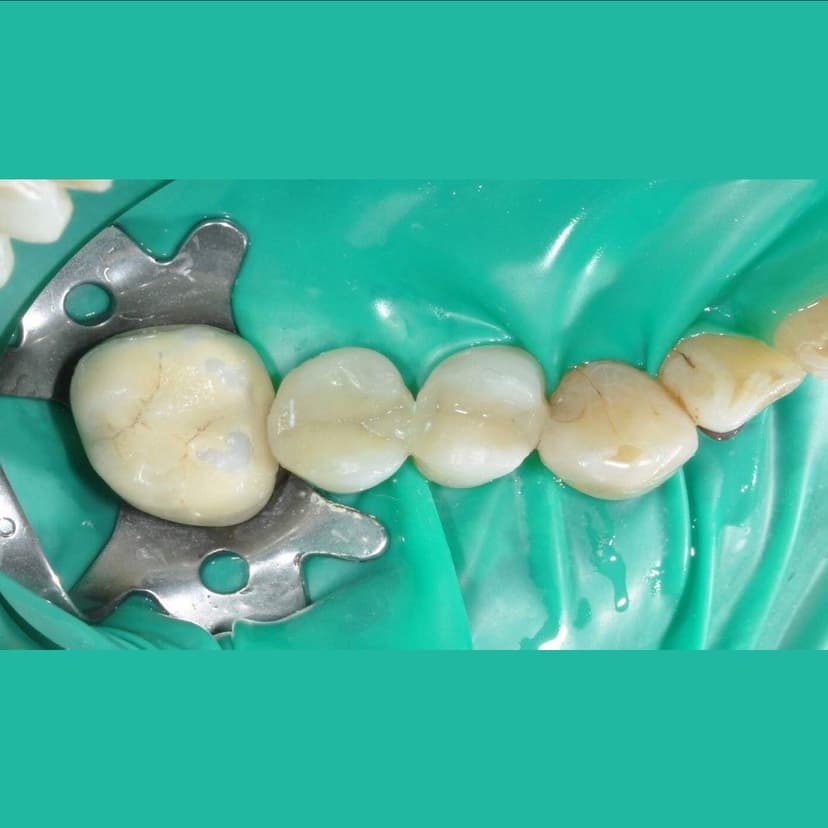

Tooth-colored fillings to restore decayed teeth

Key Features: